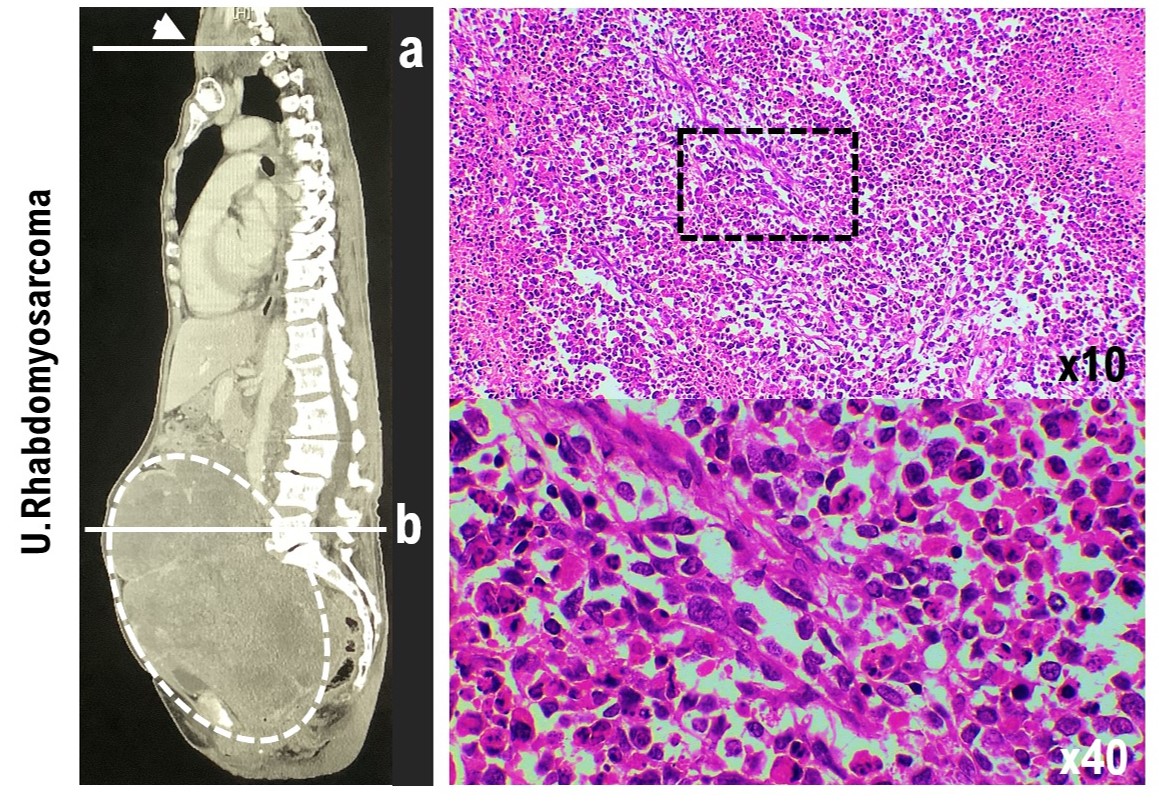

Characteristic of Uterine Rhabdomyosarcoma by Algorithm of Potential Biomarkers for Uterine Mesenchymal Tumor

Background/Aim: Patients with uterine sarcoma comprise 2%–5% of all patients with uterine malignancies; however, the morbidity of uterine sarcoma is low compared with that of other gynecological cancers. For many cases, malignant uterine tumors are diagnosed during follow-up of benign uterine leiomyoma. Of the uterine sarcomas, rhabdomyosarcoma is considered a mixed tumor containing components of epithelial cells and mesenchymal cells. Therefore, the onset of primary uterine rhabdomyosarcoma during follow-up of uterine leiomyoma is extremely rare. Rhabdomyosarcoma is a relatively common malignant tumor in children, but rhabdomyosarcoma in adults is extremely rare, accounting for approximately 3% of all patients with soft tissue sarcoma. Rhabdomyosarcoma in children is highly sensitive to chemotherapy and radiation therapy; however, the response to chemotherapy and radiation therapy in adult rhabdomyosarcoma is low and survival in adult rhabdomyosarcoma with metastatic lesions to other organs is approximately 14 months. We experienced a case of polymorphic rhabdomyosarcoma during the follow-up of a uterine leiomyoma. Materials and Methods: We examined the oncological properties of uterine rhabdomyosarcoma in adults using molecular pathological techniques on tissue excised from patients with uterine leiomyoma. Result: A differential diagnosis was made for this case by molecular pathology, which included candidate biomarkers for uterine smooth muscle tumors. The oncological nature of uterine rhabdomyosarcoma was found to be similar to the oncological properties of uterine leiomyosarcoma. However, in uterine rhabdomyosarcoma, LMP2/1i-positive cells were clearly observed. Conclusion: It is expected that establishing a diagnostic and treatment method targeting characteristics of mesenchymal tumor cells will lead to the treatment of malignant tumors with a low risk of recurrence and metastasis.